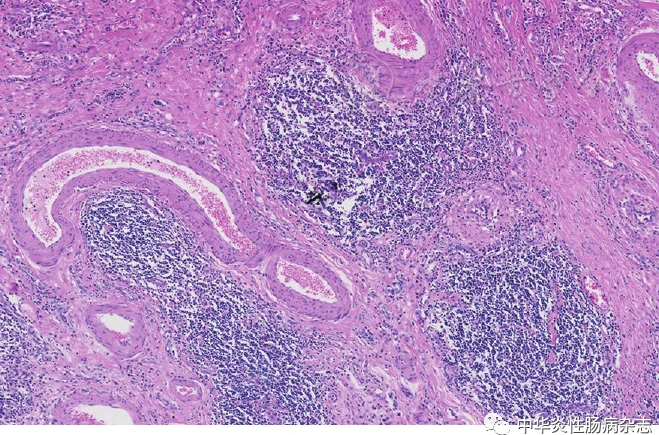

其次,克罗恩病还需要与其他消化系统疾病进行鉴别,如肠道感染、胃肠道肿瘤等。肠道感染常常伴随着腹泻、发热等症状,而克罗恩病则表现为慢性复发性腹痛、腹泻、便血等。此外,胃肠道肿瘤的症状也可能与克罗恩病相似,但通过结肠镜检查和组织活检可以明确诊断。

最后,在鉴别诊断过程中,影像学检查和实验室检查也起着至关重要的作用。例如,通过结肠镜检查可以直接观察肠道黏膜的病变情况,结合组织活检结果可以明确诊断克罗恩病。此外,血液检查中的C-